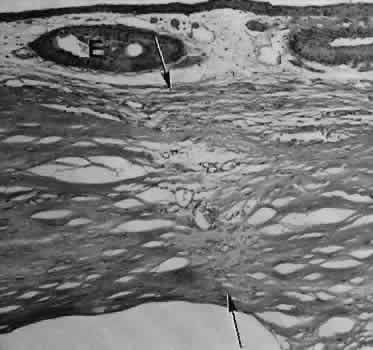

The most reliable histologic landmark of a healed cataract incision (Fig. 14) is a hiatus of peripheral Descemet's membrane. The cut edges of Desce-met's membrane will curl inward toward the sclera.Endothelial cells may be absent or may have produced a new, thin, periodic acid-Schiff-positive Descemet's membrane over exposed corneal stroma. Occasionally, a fibrous plaque is present at the level of Descemet's membrane. This plaque is another example of fibrous metaplasia, in this instance of the corneal endothelial cells. The corneal stromal portion of the wound may be difficult to identify histologically, except in the early stages of healing. Clues to the position of the intrastromal tract include residual suture material, malorientation of collagen bundles, vascularization along the route of the incision, or incarceration of pigment, lens capsular remnants, or fragments of Descemet's membrane. The superficial portion of the wound tends to heal most completely. Breaks in Bowman's membrane will be present at the site of suture tracts and clear corneal cataract incisions. Also, areas of epithelial cell inclusion may be present in the substantia propria of the conjunctiva at the conjunctival incision.

Fig. 14. Light micrograph of a well-healed limbal wound. The wound through the sclera has healed almost completely, marked only by several small caliber blood vessels. Small epithelial inclusions (E) mark the site of the overlying conjunctival incision. Descemet's membrane in this specimen remains relatively straight. (Periodic acid-Schiff stain; × 40.)